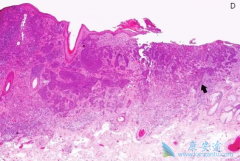

• 基底细胞癌症状有哪些?临床上有哪些治疗方法?

基底细胞癌症状有哪些?临床上有哪些治疗方法?

基底细胞癌 (BCC)是皮肤科常见的恶性肿瘤之一,它的病因与日光暴晒有密切关系,另外与各种物理及化学物质的长期刺激也有关系。好发于身体暴露部位,特别是面部,主要在眼眦、鼻部、鼻唇沟和颊部多见;其损害多为浅表性皮疹,早期症状通常为一表面光亮 ...